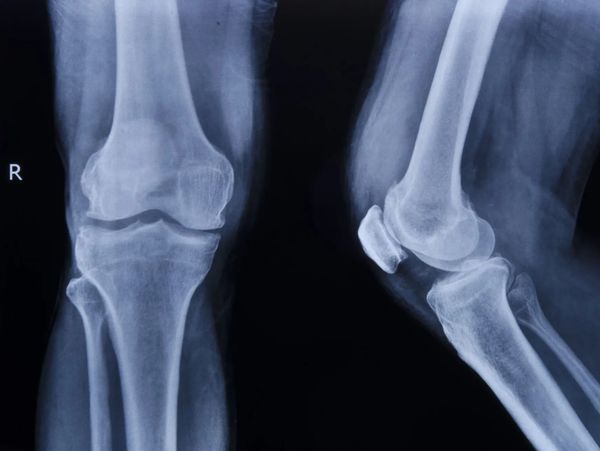

Digital radiography is used to capture images of bones and other musculoskeletal structures. It is safer than traditional x-rays as it reduces radiation by up to 90%. We have an in-house x-ray machine to help save patients time, and ensure our providers are getting the most accurate images.